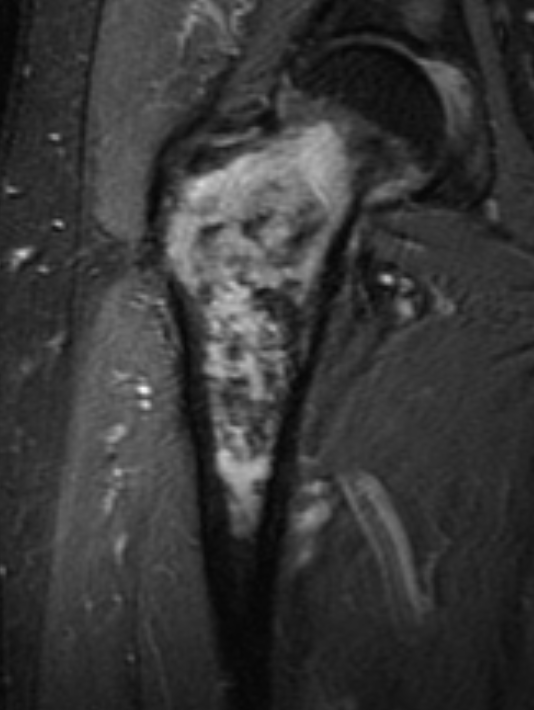

MRI

- MRI of 179 chondrosaroma

- features of high grade chondrosarcoma

- bone expansion, active periostitis, soft tissue mass and increased tumour length